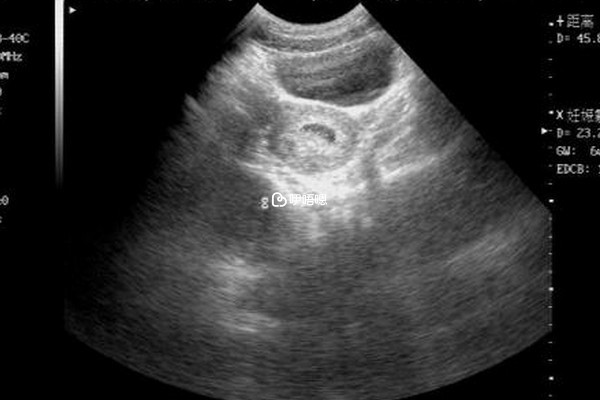

另外,女性在試管移植成功後也一定要按時、定期產檢,比如移植28天的一超等,這樣大家才能更加清楚的瞭解胎兒的情況,出現異常時好及時進行處理,另外,建議大家不要過早的進行夫妻生活,因為本身胚胎著床不夠穩定,同房容易引發子宮收縮,導致流產。